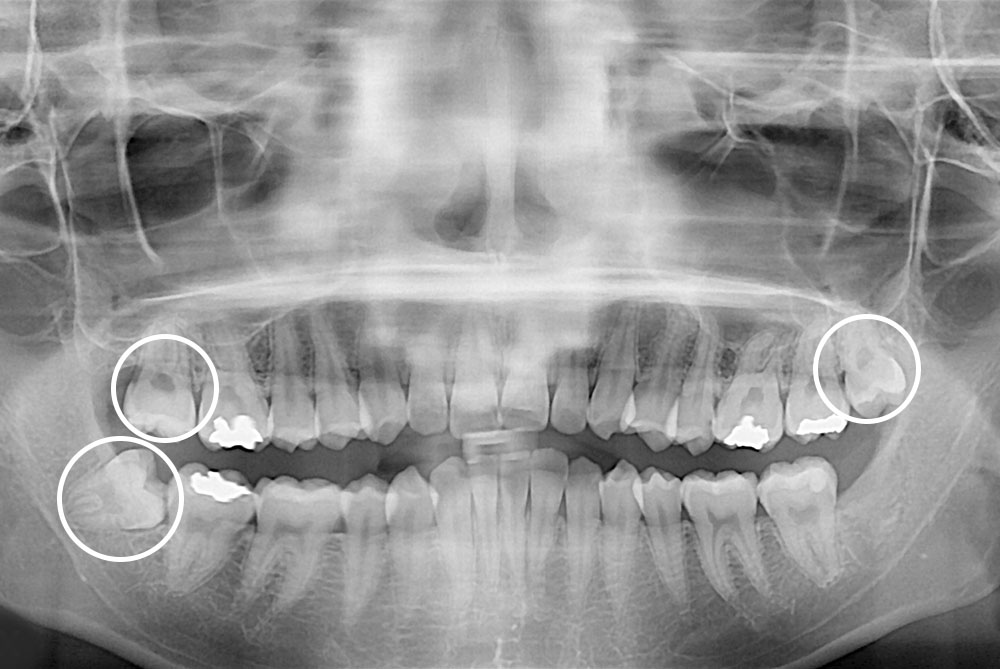

[사랑니] 매복 사랑니 발치

치료전 : 2019-08-01

세종치과는 구강악안면외과학 박사이신 원장님이 발치하는 치과입니다.